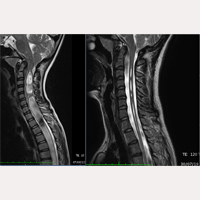

Идиопатический Сколиоз

С октября 1993 года по июль 2017 года было произведено лечение с применением FILUM-SYSTEM® более 1000 пациентов, страдающих Синдромом натяжения спинного мозга и/или Заболеванием концевой нити с Синдромом Арнольда Киари I, Сирингомиелией и Сколиозом в различных диагностических комбинациях.